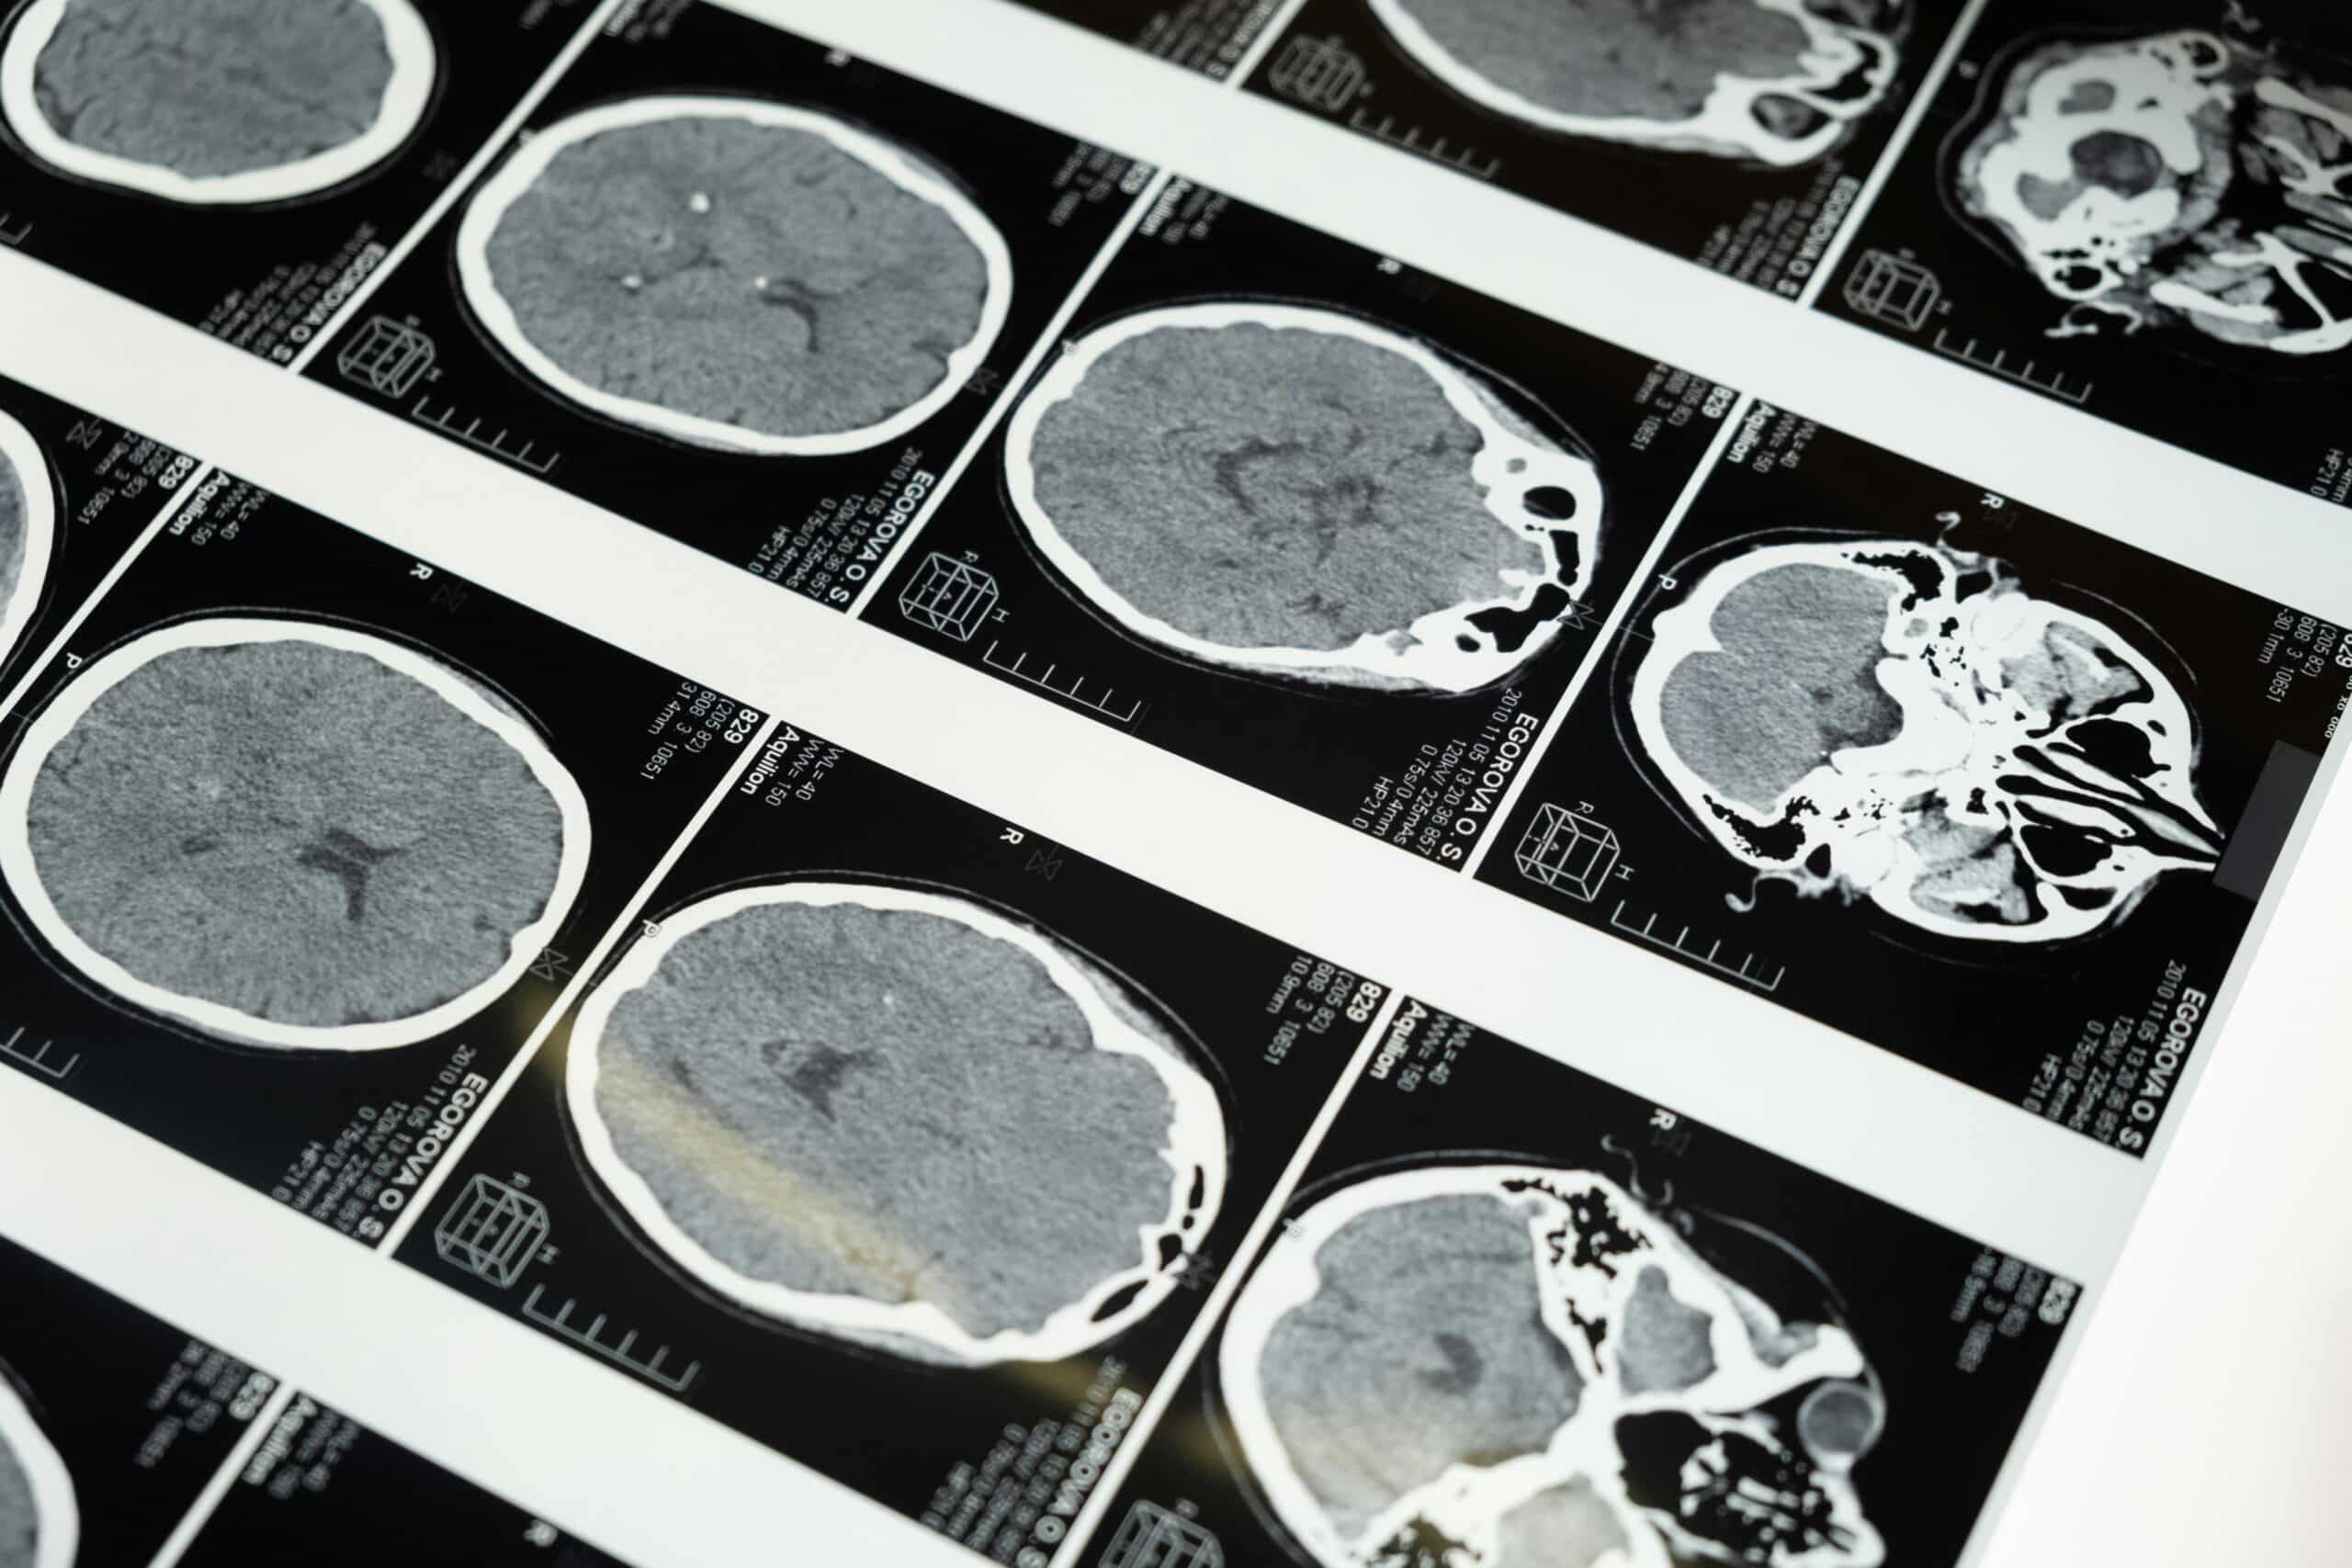

Integrative Oncology From Head to Toe – Brain Cancer

Introduction Primary brain tumours are a rare but impactful group of cancers that arise from the tissues of the brain and central nervous system. In North America, brain and other central nervous system tumours occur in about 6–7 people per 100,000 each year. While primary brain tumours account for a small percentage of all cancers, they... Read More